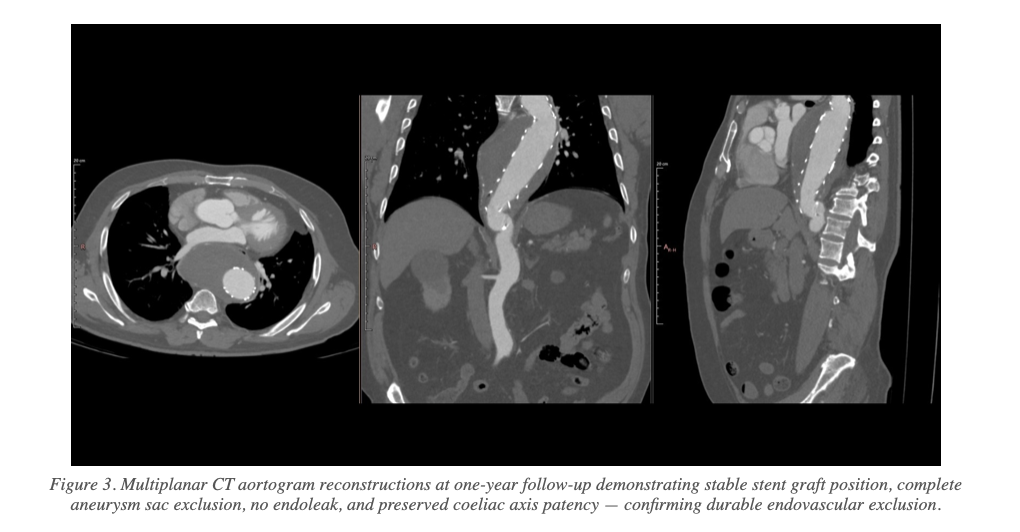

The patient had an uneventful post-procedural course. At clinical follow-up, he remained free of chest pain with significant resolution of compressive symptoms. One-year CT angiography confirmed:

- No endoleak detected

- No interval expansion of the aneurysm sac

- Stable stent graft position with good proximal and distal apposition at both landing zones

- Preserved patency of the coeliac axis

- Complete exclusion of the thoracic aortic aneurysm with satisfactory aortic remodelling